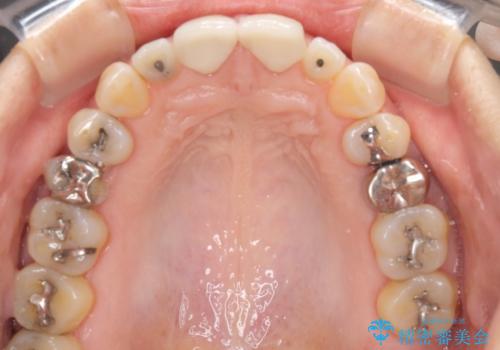

今回はまず欠けた場所を修復して見た目を回復させたのち、ラミネートべニアの仮歯をつくり、しばらく使用して考えて頂きました。メリットやデメリットを説明した結果、外れにくいセラミッククラウンをご選択頂きました。

咬み合わせや元のご自身の歯の色に特徴があったため、セラミッククラウンを修正したり、隣の歯を金属を外して白いつめものに変えたりして経過観察を長めに行いました。

右上の歯に関しても、大きな虫歯があったため、前歯の経過観察の間に治療を行いました。